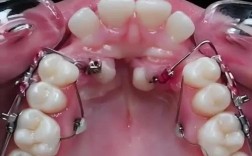

- 关闭拔牙间隙:正畸治疗中常因牙齿拥挤需拔除前磨牙,拔牙后的间隙需通过牵引牙齿向移动关闭,橡皮筋能精准控制牙齿移动方向,避免间隙两侧牙齿倾斜。

| 颌内牵引 | 单一牙弓内牙齿相互牵引(如尖牙向远中移动) | 关闭拔牙间隙、纠正牙齿扭转 | 尖牙远中牵引(将尖牙向口腔后方移动,为前牙排齐腾出空间) |

- 确认牵引方向:医生会在矫治器上粘贴“牵引钩”(或利用托槽本身的钩子),需明确橡皮筋应挂在“上颌哪颗牙的钩子”与“下颌哪颗牙的钩子”上,避免方向错误(如II类牵引方向反了会导致“龅牙”加重)。

- 挂钩操作:将橡皮筋的一端挂在上颌牵引钩上,另一端轻轻拉伸至下颌牵引钩,确保橡皮筋无扭曲、无松弛(理想状态是橡皮筋被轻微拉伸,但不过度紧绷)。